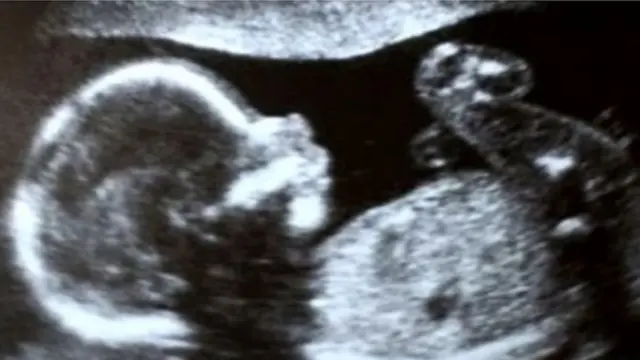

2017ஆம் ஆண்டு மே மாதம் அவருக்கு கருப்பை மாற்று அறுவை சிகிச்சை நடைபெற்றது. கடந்த ஐந்து மாதங்களாக மருத்துவமனையில் தங்கியிருக்கும் மீனாக்ஷி, தற்போது 21 வார கர்பிணி.

தாயின் சினைமுட்டையும் தந்தையின் விந்தணுவையும் சேர்த்து ஆய்வகத்தில் சோதனைக் குழாயில் உருவாக்கப்பட்ட கரு, இந்த ஆண்டு ஏப்ரல் மாதம் முதல் வாரத்தில், டாக்டர் ஷைலீஷ் மற்றும் அவருடைய குழுவினரால் மீனாக்ஷியின் கருப்பையில் வைக்கப்பட்டது.